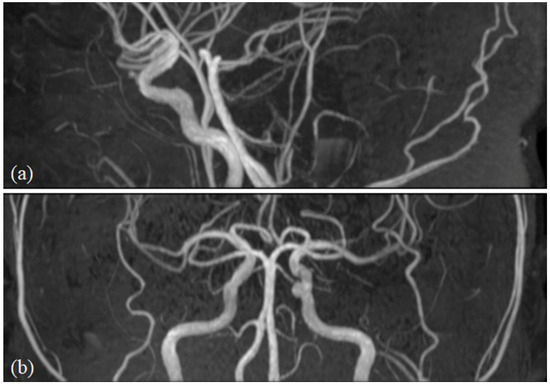

The head and neck and oral maxillofacial regions are composed of complex anatomical structures and contain various types of tissues. Radiological examination is one of the most important and widely used clinical approaches for understanding these regions. Advances in medical imaging acquisition and imaging analysis, including artificial intelligence, allow researchers and clinicians to understand the underlying physiology and pathology of these regions. These advances also offer the potential to integrate research findings to clinical practice.